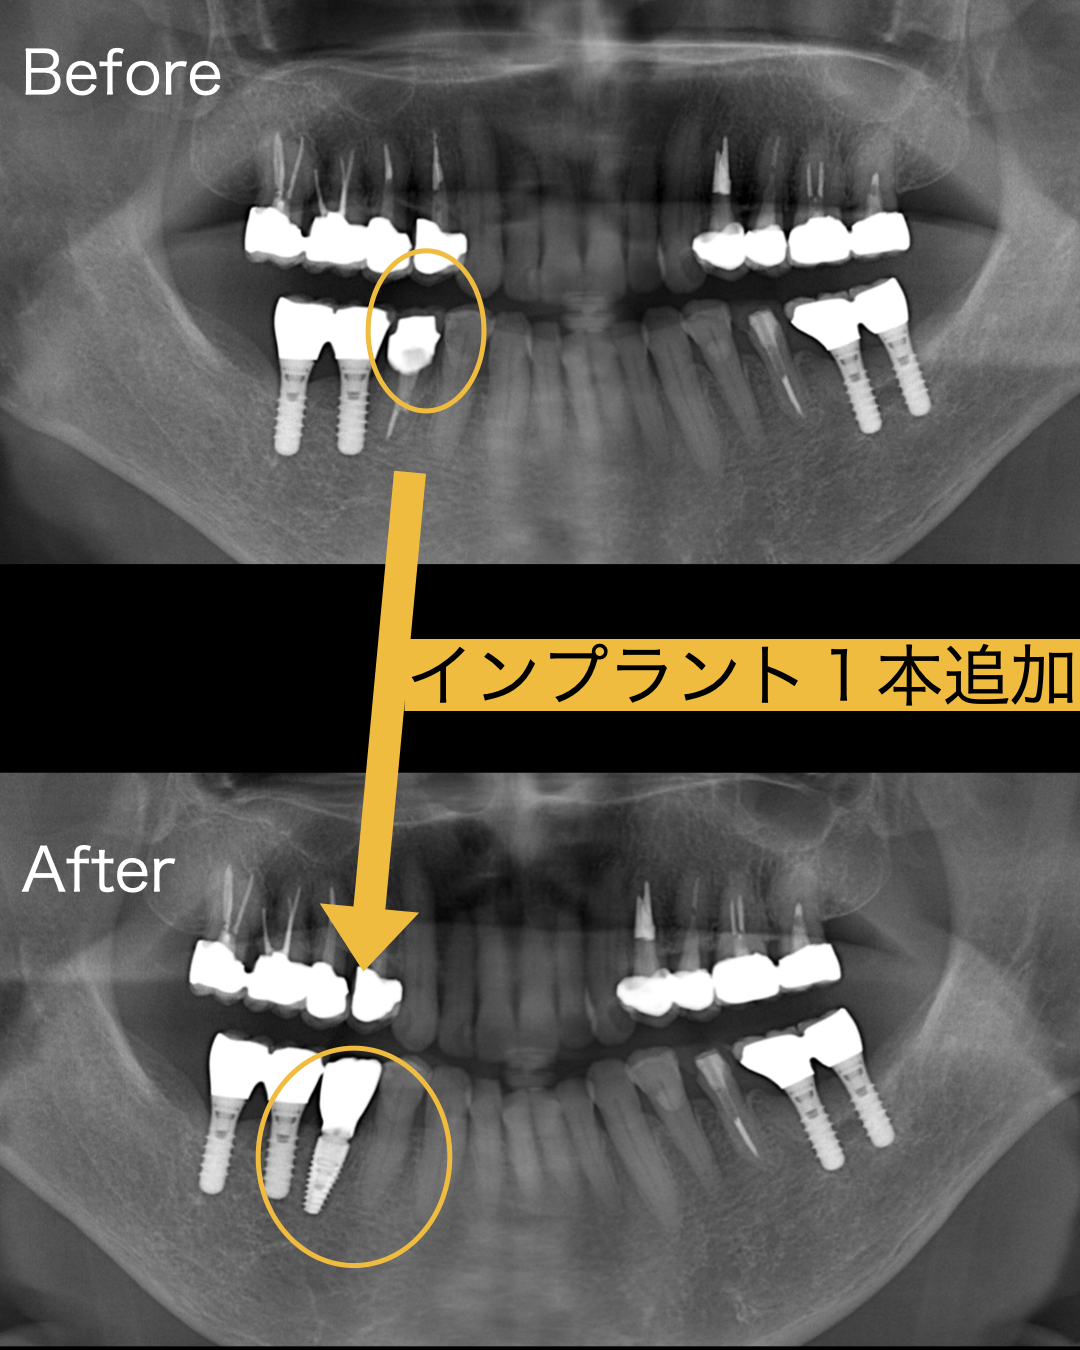

今回、歯茎が腫れてきたとのことで、見てみると歯牙が破折しており保存不可能であることお伝えしたところ、インプラントを希望され、歯を抜いてその日にインプラント入れる抜歯即時埋入を行うことになりました。

インプラント手術は抜歯に10分、インプラント埋入は15分ほどで終了しました。

問題は歯牙が破折し炎症が強かったので、少し骨のボリュームが少なくなっていました。

よって、歯を抜いてその日にインプラント埋入する、抜歯即時埋入、そして、同時に骨造成GBRを同時に行いました。術式としてはソケットシールと呼ばれる手法で骨補填材を入れたあと上部をレジンで封鎖する方法を選択しました。

痛みは全くなく、痛み止めは全く飲まなくよかったそうです。術後4ヶ月ほどで最終的なセラミックが入り患者様も大喜びでした。しかも16年前よりも手術が一瞬で終わり驚いていました。